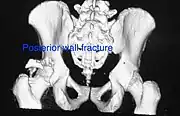

Posterior wall fracture as seen on 3-D CT scan